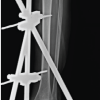

A new surgical bone biopsy, including five bacteriological samples, mycobacterial cultures, and a histopathological sample, was performed at zones of hypermetabolism identified by PET scan. The histopathological results were consistent with previous findings, while mycobacterial cultures were negative. However, all C. acnes cultures were positive 5/5. Due to the failure of non-surgical management, the patient underwent extensive surgical debridement. A sclerotic appearance without the appearance of bleeding bone was found. A horizontal anterior corticotomy for bone decompression was performed, followed by mechanical debridement with a high-speed burr and copious irrigation. The dead space was then filled with calcium sulfate Osteoset‐T® (Wright Medical Technology), loaded with tobramycin and 1 g of vancomycin, and a drain was placed (Fig. 5). Postoperatively, the patient was prescribed empirical antibiotics, including piperacillin-tazobactam 4 g intravenous (IV) 3 times/day and linezolid 600 mg IV twice daily. Assessment of the culture revealed for the third time that C. acnes samples were all positive (5/5). Afterward, the patient was treated with amoxicillin 2 g 3 times/day for 3 months, and symptoms had completely resolved by the 5-month follow-up. The calcium sulfate beads were fully resorbed 2 months postoperatively, indicating successful integration and healing (Fig. 6).